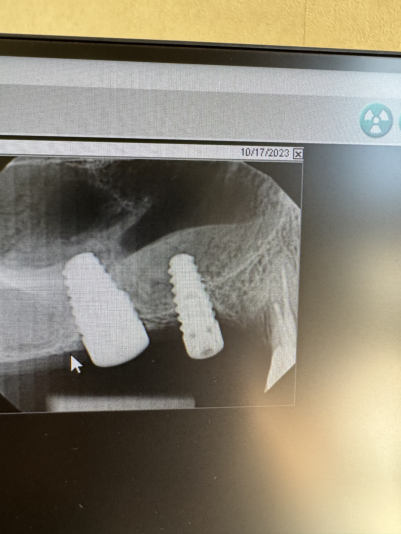

Have a patient with implants placed at 3 &4 several years ago but didn’t have the funds to restore them until now. Obviously, the anterior one doesn’t look so great radiographically (no bleeding inflammation, etc clinically). Both feel solid and pass the mirror-tapping test.

Would you guys think #3 could still be restored? I don’t think #4 should be restored, but don’t think pt is interested in explant & new implant at that site. My guess is that if we loaded #4 if would progress the bone loss that has already occurred, right?

I would remove them both and start over. The only way I’d restore 3 is if it was aware that it had less than 5 year prognosis. The issue was tissue thickness which was less than 2mm thick in all dimensions. I would just be honest with pt that their bone didn’t heal well and you’re concerned about long term prognosis. If they were hell bent I would put in a CT graft poncho style.